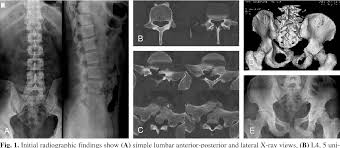

/ Transverse Process Fracture Ct : Pitfalls In The Radiographic Diagnosis Of The Transverse Processes Fracture Of The Lumbar Vertebrae Hegde Kv Umamaheswara Rv Agrawal A J Orthop Allied Sci, It may occur as an avulsion fracture due to strong contracture of the muscles.

A transverse process fracture is a break in 1 or more transverse process. There is one on both sides of every vertebra in the… a transverse process fracture is quite a rare injury. Transverse process fractures are common sequelae of trauma, although they are considered a minor and stable lumbar spine fracture. In 78% of transverse process fractures, ct scanning showed that the fracture extended into the transverse foramen. A transverse process fracture is a break in 1 or more transverse process.

A transverse process fracture at the level of l5 is a surrogate marker of vertical instability of the pelvic fracture due to the attachment of the iliolumbar ligaments. Possible causes, signs and symptoms, standard treatment options and means of care and support. Transverse processes are used as lever arms by the deep spinal muscles to maintain posture and to induce rotation and lateral bending. It may occur as an avulsion fracture due to strong contracture of the muscles. Although the fracture is not associated with spinal cord damage and neurological deficits, the extreme force of the injury can cause visceral injuries and internal hemorrhage. The presence of other injuries might also be assessed due to the level of force needed to break the transverse process. In 78% of transverse process fractures, ct scanning showed that the fracture extended into the transverse foramen. Transverse process fractures caused by stress are likely under detected since even an acute transverse process fracture requires a high index of suspicion to be correctly identified(4,7). Here is an example of a patient with a benign looking transverse process fracture with an associated significant injury to the back. Transverse process fracture you have fractured a transverse process. Thoracic transverse process fractures (ttpfs) are injuries that go unnoticed during traditional autopsies, as demonstrated by a lack of medicolegal publications regarding ttpfs. We retrospectively reviewed the reports of lumbar spine and abdominopelvic ct scans from 2017 and 2018 to classify the types of spine fractures, their mechanism of injury, treatment and. Up to 60% of lumbar transverse process fractures identified on ct will be missed on plain radiographs.

However, postmortem computed tomography (pmct) has made detection of this type of injury easy. There are two transverse processes that extend off each vertebra in the details: What is a transverse process fracture? It may occur as an avulsion fracture due to strong contracture of the muscles. It occurs as a result of sudden and extreme trauma. If ct confirms isolated injury lateral flexion/extension views are indicated to rule out dynamic instability. Vertebral angiography, performed in eight patients with fractures involving the transverse foramen, showed dissection or occlusion of the vertebral artery in seven (88%) instances. This part extends out from the side of the main body of the bone (called the vertebral body). A transverse process fracture at the level of l5 is a surrogate marker of vertical instability of the pelvic fracture due to the attachment of the iliolumbar ligaments. We retrospectively reviewed the reports of lumbar spine and abdominopelvic ct scans from 2017 and 2018 to classify the types of spine fractures, their mechanism of injury, treatment and. Up to 60% of lumbar transverse process fractures identified on ct will be missed on plain radiographs. In 78% of transverse process fractures, ct scanning showed that the fracture extended into the transverse foramen. Transverse process fractures identified on helical computed tomography (ct) scans without the presence of any other fracture or.